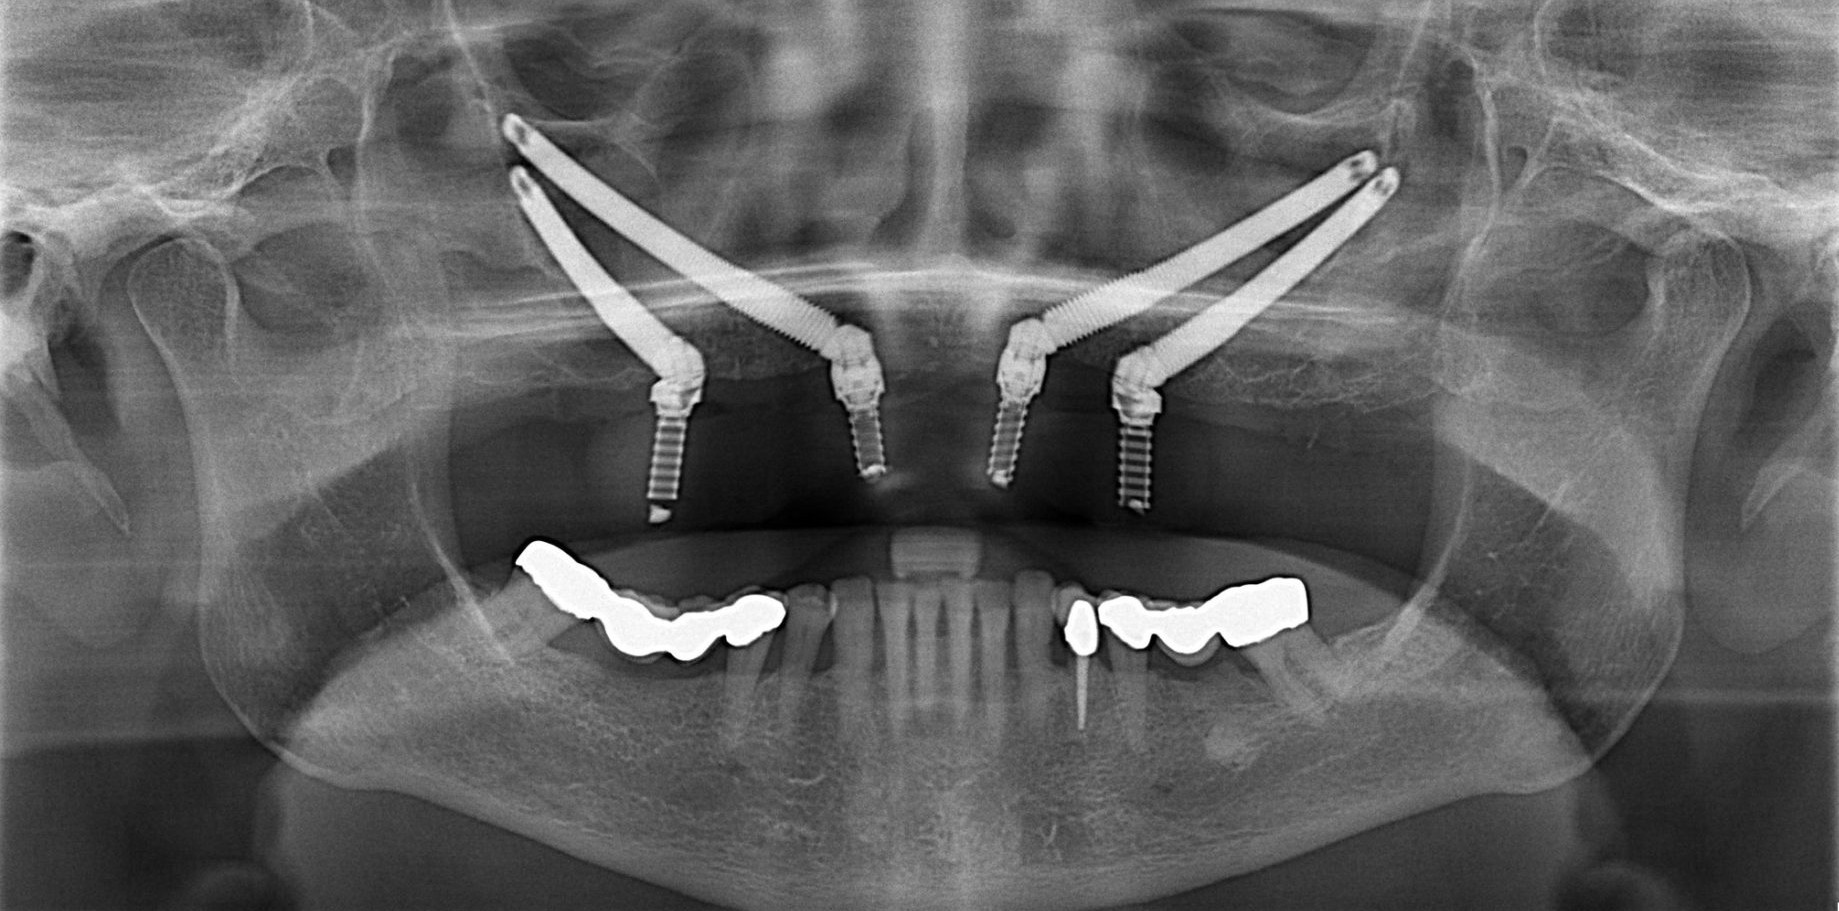

A reabilitação de maxilas atróficas sempre representou um desafio importante na implantodontia. Embora os avanços em regeneração óssea tenham ampliado as possibilidades terapêuticas, ainda existem situações